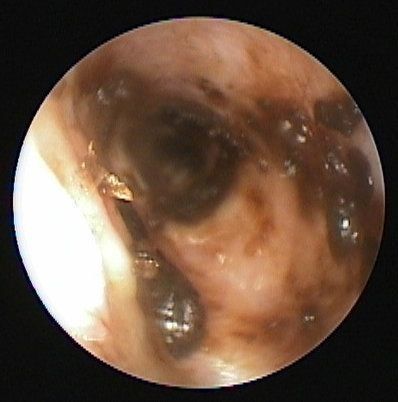

(写真上)外耳炎にかかった外耳道の内部です。炎症や腫れ、分泌物などが見られます。